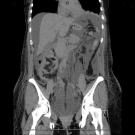

A 64-year-old man was referred to a hepatology clinic for evaluation of ascites. He had type 2 diabetes mellitus, coronary artery disease, hypertension, hyperlipidemia, and end-stage renal disease (ESRD). ...